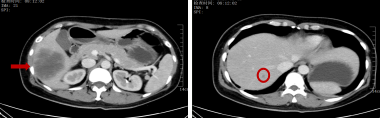

治疗前:肝脏多发转移瘤

治疗后:肝右叶转移瘤显著缩小,

其余小转移瘤消失

2024-12-26 开始患者进行「贝伐珠单抗 500 mg d1+奥沙利铂 200 mg d1+卡培他滨 1 g 1/早餐后 1.5 g 1/晚餐后 d1-14 Q3w」方案治疗,在 2 周期治疗后患者黑便消失,腹痛、腹泻缓解,贫血改善,血红蛋白升至 91 g/L,体力状况恢复(ECOG:0 分),生活质量明显提升,复查上腹部+盆腔 CT:结肠肝曲病变稳定,肝脏异常强化影较前明显缩小,最大约 7.3 cm×6 cm,初步治疗后疗效显著。继续 6 个周期的系统治疗后,全面复查结果带来了振奋人心的消息:肿瘤标志物大幅下降,CEA(正常值<5ng/ml)从初始的 23.2ng/mL 降至 2.3ng/mL,CA199(正常值<30U/ml)从 479U/mL 降至 25U/mL,肝脏小的转移灶消失,最大的转移灶从 11 cm 显著缩小至 6 cm,原本广泛的肝转移灶得到了有效控制,这意味着转化治疗取得了成功,原本无法手术的晚期病灶,终于退缩到了可以手术切除的范围。